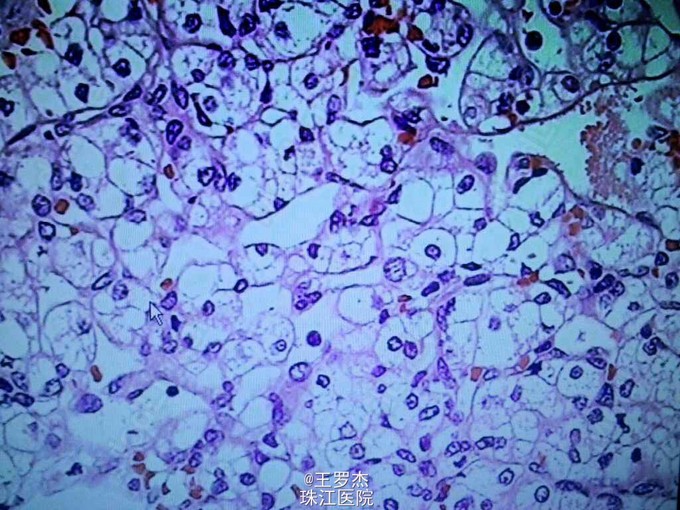

肾透明细胞癌 肾囊肿

术前诊断:左肾癌,嗜铬细胞瘤。 由于不典型嗜铬细胞瘤可表现血压正常,为减少手术风险,术前给予利脉和陪他洛克,监测血压心率。3周后血压控制平稳,完善检查后进行手术。 腹腔镜下肾上腺切除术+肾部分切除术+左肾囊肿去顶减压术。术后诊断:左肾透明细胞癌,左肾上腺结节状增生。

VHL综合征是罕见的常染色体显性遗传肿瘤综合征。主要表现为中枢神经系统和视网膜血管母细胞瘤及内脏良恶性肿瘤或囊肿。肾透明细胞癌也常见,但不适宜根治性肾切除,因为是多器官肿瘤,双侧肾脏都可能大病,根治切除只会加速透析的进程,生活质量低,而因其肾脏存在多数微小癌灶或者即将恶变的病灶,部分切除后仍需要定时检查。及早发现,一般认为大于3cm可行手术部分切除。有人认为vHL患者肾囊肿有可能发展为肾癌,但一般只需去顶减压,不宜过度治疗。